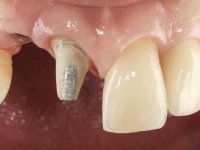

Paciente do sexo feminino, com 36 anos de idade, não fumadora. Apresentava o dente 1.1 com uma tonalidade mais escura que os dentes adjacentes. Feito o exame imagiológico, observou-se que o dente 1.1 tinha tratamento endodôntico, a paciente tinha 3 implantes colocados, dois no local dos dentes 1.2 e 2.2 e o outro no 4.6. A paciente tinha sido tratada ortodonticamente, apresentava um fenótipo gengival médio e uma boa higiene oral. Após 5 anos da primeira intervenção a paciente apresenta-se na consulta com sintomatologia infeciosa compatível com uma peri-implantite nos implantes 1.2 e 4.6. Após exame clínico, foi confirmada imagiológicamente. A perda óssea vertical tinha mais de 4mm nas duas situações.

Após 5 anos da primeira intervenção, a paciente surge na consulta com uma peri-implantite nos implantes colocados no local dos dentes 1.2 e 4.6. Começamos por abordar a peri-implantite no local do dente 2.2. Foi feita uma ponte provisória de laboratório em acrílico com 2 elementos. O dente 1.1 como pilar e o 1.2 como pôntico, este último apresentava um apoio distal. A coroa do 1.2 foi removida do coto com um corte longitudinal feito com turbina e depois foi fraturada com um mini luxador. O coto foi de seguida desaparafusado do implante. Fez-se o mesmo procedimento para remover a coroa do 1.1. O dente 1.1 foi re-preparado e a ponte provisória foi rebaseada em boca com acrílico autopolimerizável. Feito o correto acabamento e polimento da provisória foi feita a sua cimentação temporária com cimento de policarboxylato. Numa consulta posterior. foi feita a remoção da ponte provisória, feita a cirurgia para explantação do implante, colocou-se um novo implante e fez-se a regeneração óssea da zona com uma membrana não reabsorvível. 3 meses após foi removida a coroa do implante colocado no 4.6. Foi feito um corte horizontal com turbina na zona cervical e com um mini luxador descolou-se a coroa do coto. Após este procedimento fez-se a explantação do implante. Após 6 meses foi colocado um novo implante no local do 4.6. Após a osteointegração foi feita a impressão com a técnica de moldeira aberta e foi confecionada em laboratório uma coroa aparafusada sobre o implante. Aprovada pela paciente foi apertada definitivamente em boca. Após 1 mês removemos a ponte provisória antero-superior, reforçamos o dente 1.1 com um poste intra- radicular e reconstruimos o coto com uma resina de polimerização dual. Nessa mesma consulta expomos o implante colocado no 1.2 e fizemos uma impressão pela técnica de moldeira aberta com silicone de dupla viscosidade e presa rápida. No laboratório foi feita uma ponte provisória de 2 elementos, aparafusada sobre o implante e cimentada sobre o dente. A primeira ponte provisória foi removida e colocada a segunda aparafusada sobre o implante. A linha de acabamento cervical do 1.1 foi rebaseada com resina composta durante o aperto do parafuso do implante. Depois foi removida, foram feitos os acabamentos e finalmente apertada sobre o implante e cimentada temporariamente sobre o dente. Após 2 meses de maturação dos tecidos moles em função do perfil de emergência criado pela nova ponte provisória, pudemos avaliar a estética conseguida em conjunto com a paciente. Neste longo processo o dente 2.1 teve que fazer um tratamento endodôntico. Decidiu-se assim fazer também uma coroa no dente 2.1.O dente 2.1 foi preparado na mesma consulta em que se fez a impressão ao implante. A ponte provisória foi utilizada para individualizar a peça de transferência, copiando o seu perfil de emergência e em seguida foi realizado o afastamento gengival com caolino. A impressão foi feita com a técnica de moldeira aberta com silicone de dupla viscosidade e presa rápida. Após a escolha da cor, a impressão foi enviada  para o laboratório onde foram confecionadas 2 coroas  com infraestrutura em Zr. revestidas a cerâmica para os dentes 1.1 e 2.1 e uma coroa aparafusada sobre o implante no dente 1.2. O trabalho final foi aprovado pela paciente e foi colocado definitivamente em boca. A coroa sobre o implante foi aparafusada com 35 N e as coroas foram cimentadas com cimento de ionómero de vidro reforçado com resina.